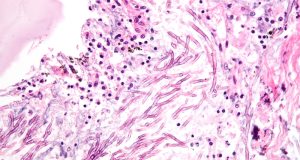

Fungal disease revealed to be a large scale threat to Indian...

While diseases such as tuberculosis and HIV are at the forefront of media attention regarding infectious disease, one threat has long gone overlooked –...